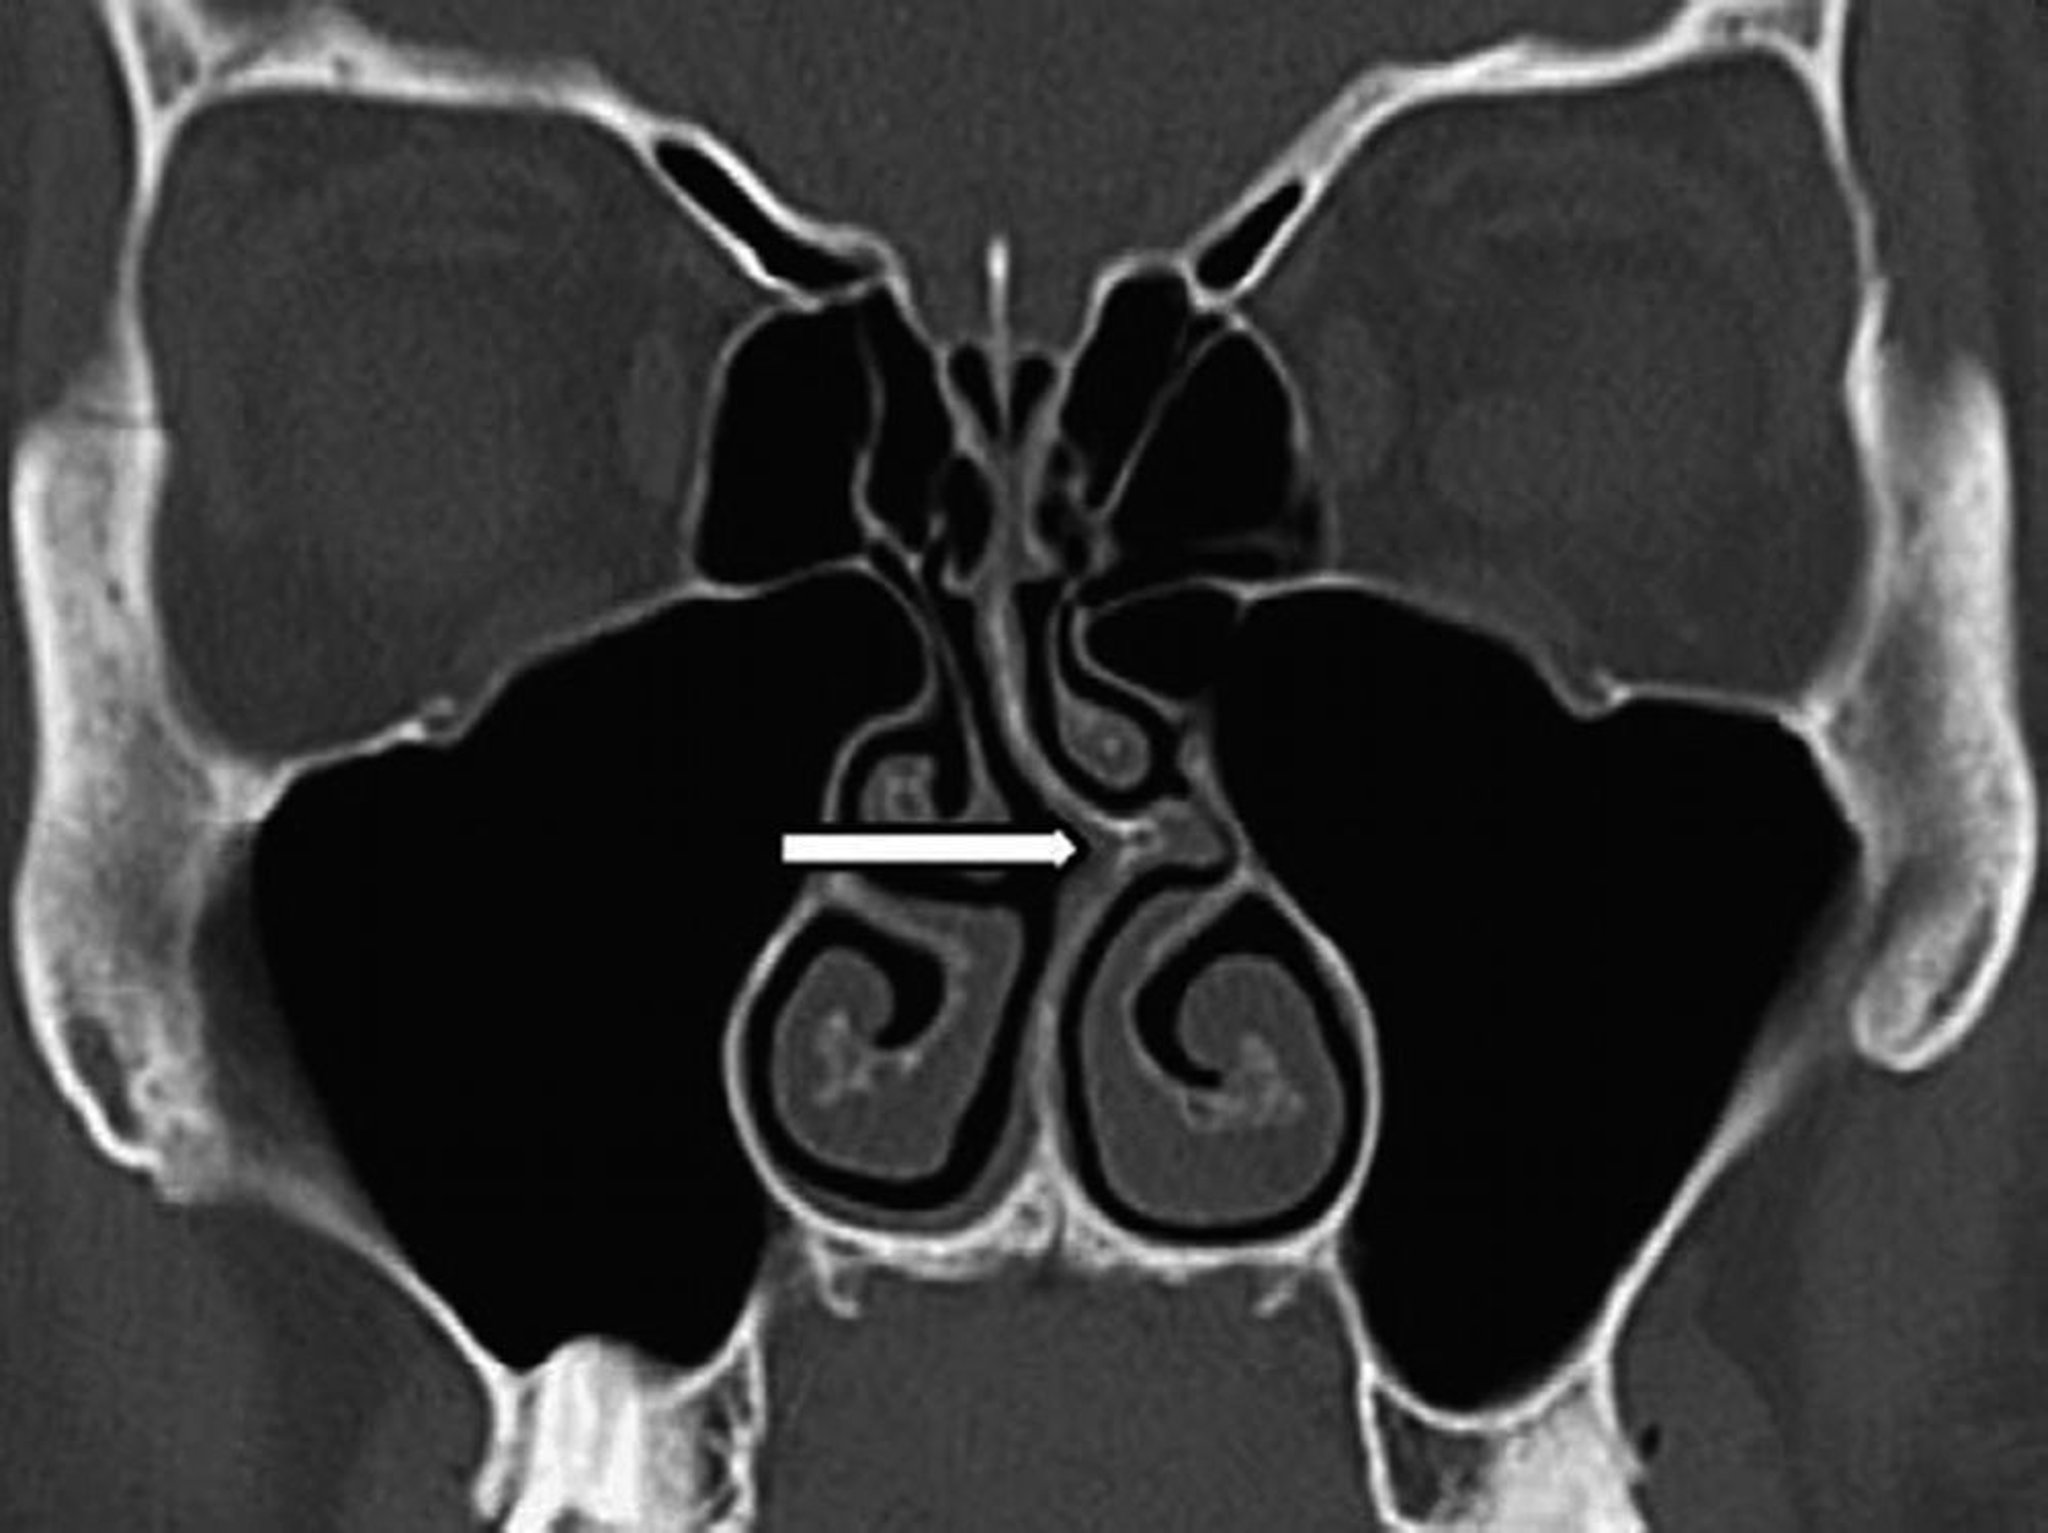

Septumdeviation (CT)

Dieser koronale CT-Scan zeigt eine Abweichung der Nasenscheidewand nach links (Pfeil).